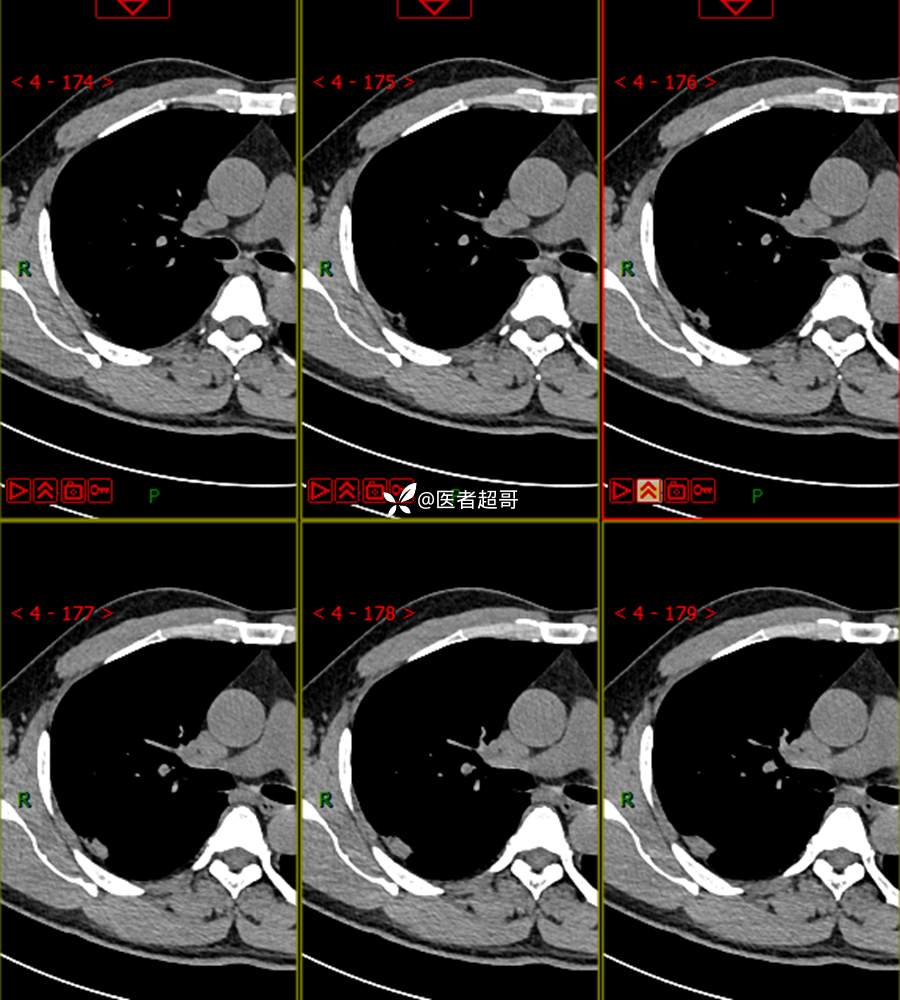

现病史:患者1年余前于体健中心行胸部X片发现右上肺叶密度增高影,无明显咳嗽,咳痰,无痰中带血及咯血,无胸痛及胸闷、气短,无发热、盗汗及全身乏力。无头痛、头晕,无腹痛、腹胀及恶心、呕吐,无声音嘶哑及呛咳,未行特殊治疗。后患者定期复查胸部CT,未见明显变化。2023-2-6患者于我院复查胸部CT:右肺上叶、下叶交接处胸膜下见实性结节影,最大截面约2.6cm×1.4cm,较前增大,建议行手术治疗。今为求进一步诊治,遂来我院就诊,门诊以“肺肿物”收入我院,患者自发病以来,神志清,精神可,饮食可,睡眠良好,大小便正常,近期体重未见明显增减。